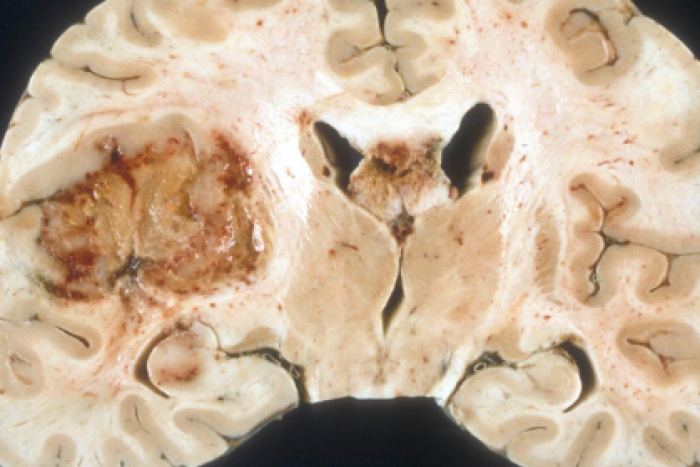

1.1. Algoritmo diagnóstico y terapéutico de las metástasis cerebrales

1.2. Papel de la cirugía y radiocirugía en el tratamiento de las metástasis cerebrales